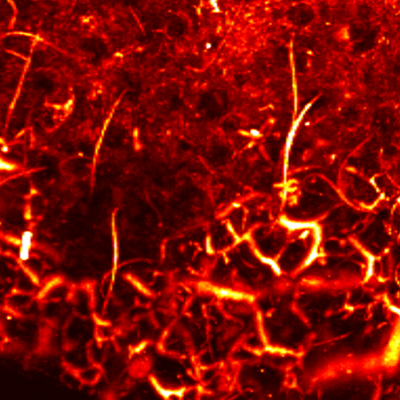

MAP

Cross sectional view

Surface(Depth) view